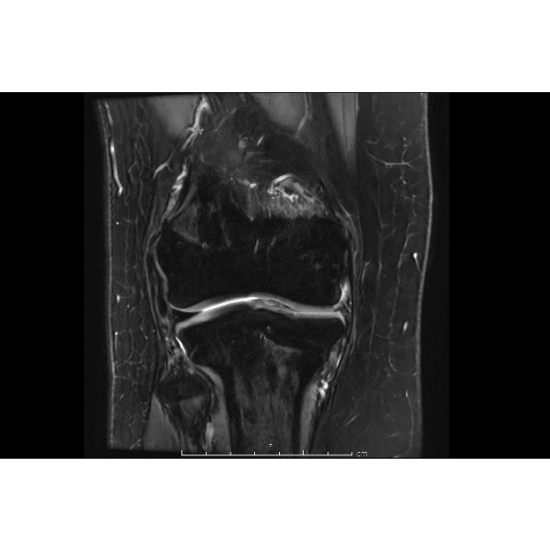

| Teenage Girl Knee-ding Some Stability - Page #3 | |||